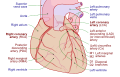

الفرع الأمامي بين البطينين للشريان التاجي الأيسر

| الشريان النازل الأمامي الأيسر Left anterior descending artery | |

![]() Sternocostal surface of heart. Anterior descending branch labeled at upper right | |

| Source | الشريان التاجي الأيسر |

| Branches | septals, diagonals |

| يـَمـِد | anterolateral عضلة القلب، apex, interventricular septum, 45-55% من البطين الأيسر (LV) |

الشريان النازل الأمامي الأيسر (left anterior descending artery، ويُختصر LAD، الفرع الأمامي بين البطينين للشريان التاجي الأيسر anterior interventricular branch of left coronary artery، أو الفرع النازل الأمامي anterior descending branch) هو فرع من الشريان التاجي الأيسر. ويزود بالدم الجزء الأمامي من البطين الأيسر.[1] وهو مسئول عن إمداد نحو نصف الإمداد الشرياني إلى البطين الأيسر وبذلك يعتبر أهم وعاء دموي يمد البطين الأيسر.[بحاجة لمصدر] انسداد هذا الشريان كثيراً ما يُسمى الجلطة صانعة الأرامل widow-maker infarction بسبب خطر الوفاة العالي لها.[2]